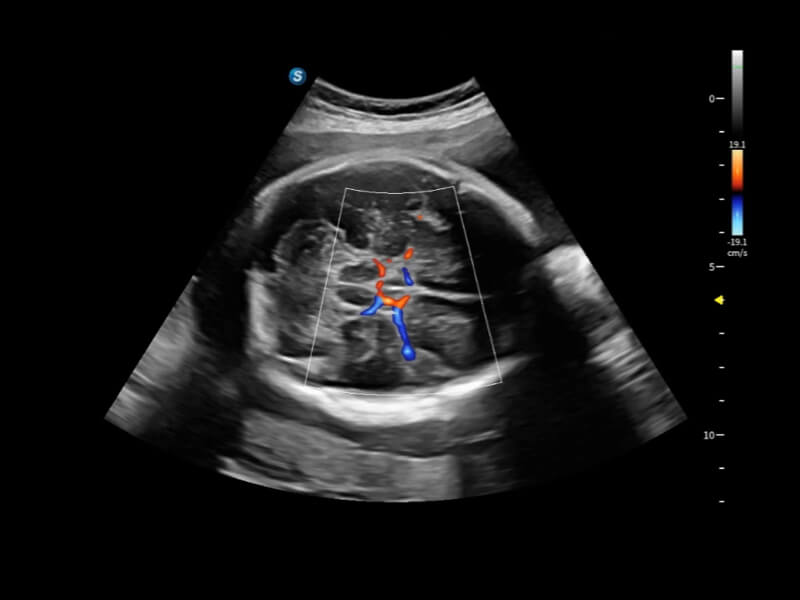

Fein abgestimmte hämodynamische Lösung

Eine Vielzahl hämodynamischer Diagnosetechniken ermöglicht eine effektive Blutflusssignaldetektion in verschiedenen Szenarien.

• Bright Flow

Bright Flow bietet eine 3D-ähnliche Farb-Doppler-Flow-Visualisierung ohne den Einsatz eines Volumenwandlers, wodurch die Grenzdefinition der Gefäßwände verstärkt wird.